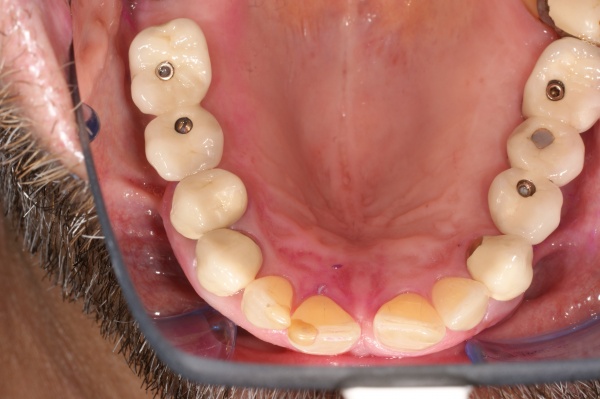

Aufgrund der parodontalen Destruktion, die letztlich erst mit dem intraoperativen Befund dreidimensional beurteilt werden konnte, mussten die Zähne 17, 26 und 27 als langfristig nicht erhaltungswürdig beurteilt werden. Da mit ihrem Verlust auch keine ausreichenden natürlichen Pfeiler mehr für einen definitiven festsitzenden Zahnersatz zur Verfügung standen, wurde eine implantatprothetische Versorgung mit zwei Implantaten in regio 15, 16 und drei Implantaten in regio 24, 25, und 26 geplant. Die Implantation und die entsprechenden präimplantologisch-augmentativen Maßnahmen wurde in der kieferchirurgischen Ambulanz (FU VIIb, Leiter Prof. Dr. Dr. K.O. Henkel) durchgeführt. Eine zwingende Indikation zur Versorgung der Freiendsituation ab 36 und der Schaltlücke bestand nicht, sodass in Übereinstimmung mit dem Patienten für den Unterkiefer kein Zahnersatz geplant und angefertigt wurde. Nach Wiedervorstellung im Oktober 2003 wurde die implantatprothetische Versorgung mit der Eingliederung der implantatgetragenen Kronen 15, 16, 24, 25, und 26 im November 2003 abgeschlossen. Mit der Eingliederung von Einzelkronen an 14, 13 und 23 im Februar 2004 wurde die Behandlung insgesamt abgeschlossen (s. Abb. 6). Die ursprünglich angedachte Extraktion der Molaren 17 und 28 wollte der Patient nicht mehr durchführen lassen.

Ab dem Februar 2004 wurde der Patient zur Sicherung des Behandlungserfolges in das in der FU VIIa – Zahnmedizin seit 1996 praktizierte Recallsystem aufgenommen. Diese Erhaltungstherapie beinhaltet die bereits erwähnten Maßnahmen der Unterstützenden Parodontitistherapie (UPT). Aufgrund dienstlicher Erfordernisse (u. a. immer wieder Seefahrten des Patienten) konnte der zunächst geplante Abstand von vier Monaten nicht immer eingehalten werden. Ein Abstand von ca. sechs Monaten konnte jedoch trotz der teilweise schwierigen Rahmenbedingungen realisiert werden. Am Zahn 44 kam es im Jahr 2006 zu einem Rezidiv, sodass an diesem Zahn im September 2006 eine Lappenoperation durchgeführt wurde. Der intraoperativ vorgefundene tiefe cirkuläre vertikale Defekt führte zur Einschätzung einer langfristig fraglichen Prognose von 44. Im Zuge der weiteren Erhaltungstherapie zeigten sich bis auf 44 die parodontalen und periimplantären Gewebe völlig unauffällig: So betrugen die Sondiertiefen bei entzündungsfreien klinischen Verhältnissen durchweg zwei bis drei Millimeter. Auch radiologisch zeigten sich keine Auffälligkeiten. Es gab keine Progredienz der ehemaligen parodontalen Erkrankung, die Osseointegration der Implantate zeigte keine Veränderungen (s. Abb. 7). Erhöhte Sondiertiefen verblieben lediglich am Zahn 44. Nachdem sich trotz regelmäßiger Nachsorge an 44 keine Entzündungsfreiheit der marginalen Gingiva erzielen ließ und die Zahnlockerung von 44 zunehmend stärker wurde, erfolgte im Jahre 2010 die Entfernung des Zahnes und der Ersatz durch eine implantatgetragene Krone (s. Abb. 8). Die Erhaltungstherapie wurde fortgeführt, Behandlungsmaßnahmen über die Inhalte der UPT hinaus waren bis zur Entlassung des Soldaten im Jahre 2012 nicht erforderlich. Der Patient blieb jedoch auch nach der Entlassung aus dem aktiven Dienst Patient des Hauses, sodass die Erhaltungstherapie in der FU VIIa – Zahnmedizin fortgeführt werden konnte. Im April 2013 stellte sich der Patient mit Beschwerden am Zahn 45 vor, der Zahn wies zudem eine Lockerung des Grades II auf. Die durchgeführte Röntgendiagnostik (s. Abb. 9) zeigte eine Wurzelfraktur im apikalen Wurzeldrittel, ein Zahnerhalt von 45 war nicht möglich und der Zahn wurde noch in gleicher Sitzung entfernt. Zur Versorgung der Lücke wären verschiedene prothetische Lösungen möglich gewesen. Letztlich fiel die Entscheidung zugunsten eine Extensionsbrücke von regio 45 auf 48. So konnte die Implantatkrone 44 belassen und mit dem Lückenschluss mittels einer vergleichsweise einfachen und schnellen prothetischen Versorgung auch die Schaltlücke 46 geschlossen werden. Der Patient befindet sich nach wie vor in der FU VIIa in der Erhaltungstherapie, die Fotos zeigen den aktuellen klinischen Befund in der Aufsicht des Ober- und Unterkiefers (s. Abb. 10, 11).